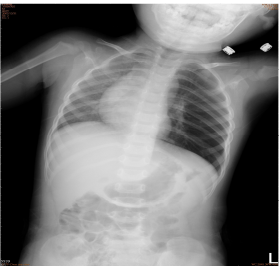

1.14個月大的男生,出現咳嗽並有呼吸急促已有10天,因為一直沒有發燒,直到媽媽發現他食慾不振 的情形才到門診求治,肺部聽診時發現兩側都可以聽到喘鳴聲(wheezing),左側呼吸音比右側小 聲,胸部X光片檢查如圖所示,下列何者是最有可能的診斷? (A)呼吸道異物 (B)先天性心臟病 (C)臟器轉位症候群 (D)左側氣胸